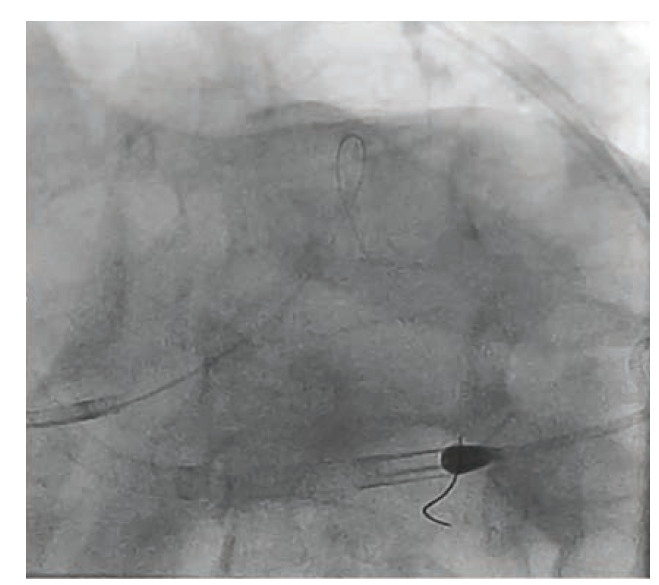

To illustrate this point, we present the case of an 86-year-old male with diabetes mellitus, paroxysmal atrial fibrillation (anticoagulated with apixaban), hypercholesterolemia, and left bundle branch block who presented to the emergency department with acute onset chest pain, shortness of breath and hypotension with a blood pressure of 88/62 mmHg. The patient was diagnosed with non-ST-elevation myocardial infarction (NSTEMI) and was emergently transferred to the cardiac catheterization lab, where the patient underwent left and right heart catheterization. Right heart catheterization demonstrated low cardiac output with elevated filling pressures. Coronary angiography revealed a codominant system, calcified Medina 1,1,1 critical left main disease, and ostial right coronary artery (RCA) disease (Figure 1).

Given these findings and systemic hypotension, an intra-aortic balloon pump (IABP) was placed and the patient was transferred to our hospital for coronary artery bypass grafting (CABG) evaluation. Due to advanced age, high frailty index, and patient preference, he was not considered to be a good surgical candidate and within 24 hours, he was brought back to the cardiac catheterization lab for intervention.